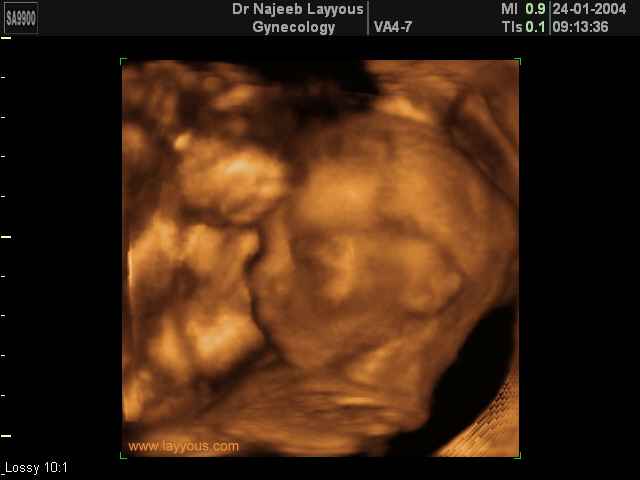

- Fetal Behavior Ultrasound Photos